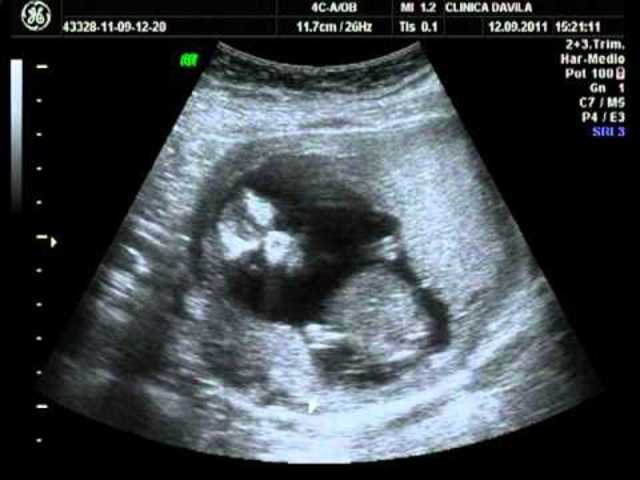

• Semanas 9 a 12

Semanas 9 a 12

Los párpados se cierran y no se vuelven a abrir casi hasta la semana 28

La cara está bien formada

Las extremidades son largas y delgadas

Los genitales aparecen bien diferenciados

Los glóbulos rojos se producen en el hígado

El tamaño de la cabeza corresponde casi a la mitad del tamaño del feto

El feto puede empuñar los dedos

Aparecen los brotes dentarios

• Semanas 13 a 19

Semanas 13 a 19

El feto tiene una longitud cráneo-caudal de unas 3 pulgadas (8 cm). A veces, ya se puede ver el sexo del feto mirando los órganos externos en un ultrasonido.